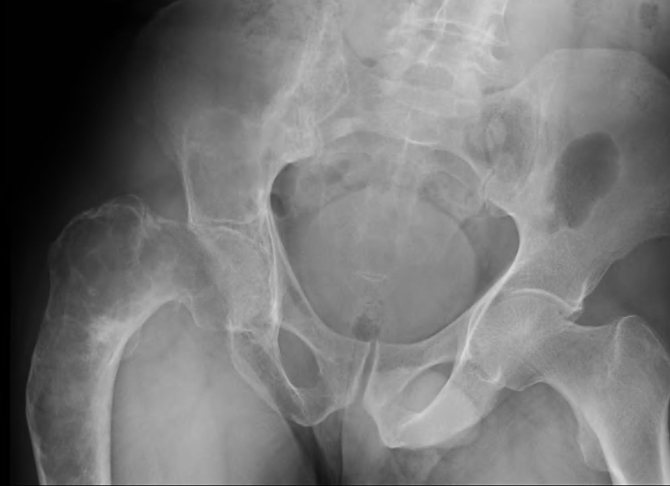

- Гинекологический осмотр. Бимануальное исследование позволяет выявить округлое эластическое образование в проекции придатков. В большинстве случаев опухоль односторонняя, поверхность ее может быть гладкой или бугристой.

- Ультразвуковое исследование. При УЗИ текома определяется как округлое гипоэхогенное образование с четкими контурами. Внутренняя структура обычно однородная, без очаговых включений. При допплерометрии кровоток внутри доброкачественной опухоли отсутствует.